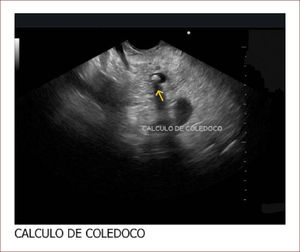

El 60% de las endosonografías remitidas a nuestro servicio, corresponde a pacientes con ictericia y sospecha de coledocolitiasis. En esta patología, la sensibilidad del EUS es mayor del 95%, como concluimos en un estudio próximo a publicarse, en el que los criterios de inclusión fueron pacientes con sospecha de cálculos del colédoco, EUS positivo para esta etiología y que nosotros mismos realizáramos la CPRE. Como se mencionó, en el 95% de los pacientes en los que el EUS mostró la presencia de cálculos en la vía biliar, coincidió con los hallazgos de la CPRE. Llamativamente, hubo 13 pacientes con MRI previa negativa para cálculos y que se remitieron por la persistencia de signos y síntomas sugestivos de cuadro litiásico, que solo pudieron ser demostrados con el EUS. El 5% restante de los pacientes diagnosticados por EUS como positivos para cálculos y sin correspondencia con los hallazgos de la CPRE, obedece posiblemente a la interpretación equívoca de imágenes o porque al momento de la CPRE, los cálculos ya hubieran salido espontáneamente a la luz intestinal. Figuras 3 y 4.

El paciente con ecografia y además imágenes que no mostraban compromiso de la vía biliar, ni de la vesícula. La resonancia magnética mostró vía biliar normal y descartó cálculos. El EUS mostró un cálculo pequeño menor de 3mm. Fue llevado a CPRE en forma temprana y el cuadro mejoró muchísimo. Hay que notar que la Resonancia a veces no detecta cálculos menores de 3mm.

Conclusión: El EUS en pancreatitis aguda tiene relevancia cuando se sospecha que la etiología es por cálculos biliares, pues su sensibilidad a este respecto es mucho mayor que la colangiorresonancia, detectando cálculos menores de 3mm. Por esta razón, como protocolo de nuestro servicio, los pacientes con pancreatitis, ictericia o colangitis, en los que otras imágenes diagnósticas no mostraron la posible causa del cuadro, se realizó una endosonografía bilio-pancreática y en caso de comprobar cálculos, lo hizo a una CPRE, en forma inmediata (solo basta cambiar el instrumento de trabajo). Con esta conducta, se optimizó la calidad del servicio prestado a nuestros pacientes, el tiempo de recuperación y de hospitalización se redujeron y el pronóstico mejoró.